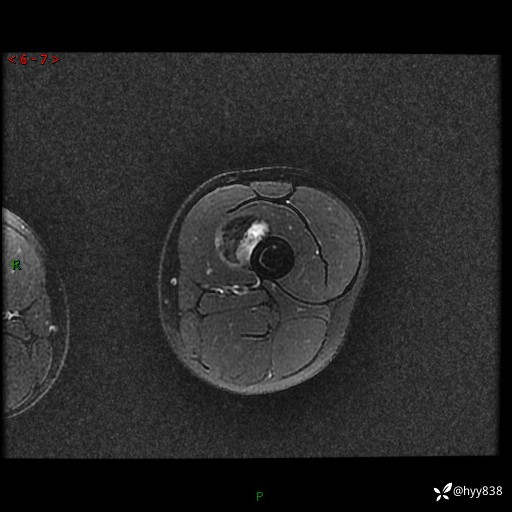

左大腿MRI平扫+增强